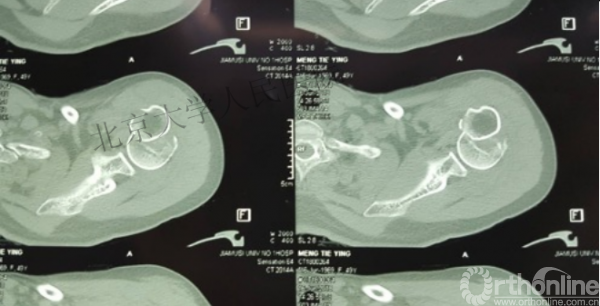

内侧皮质粉碎,低位外科颈骨折,肱骨头-干角维持困难。

术后复位丢失,肱骨头内翻畸形。

能否该偏心固定(钢板)为髓内固定,增加力臂?

此时对比髓内钉是不是有很大优势?